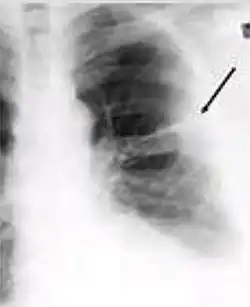

-

Chest x-ray showing dense opacity pleural effusion in the lower left lung of primary pulmonary TB.